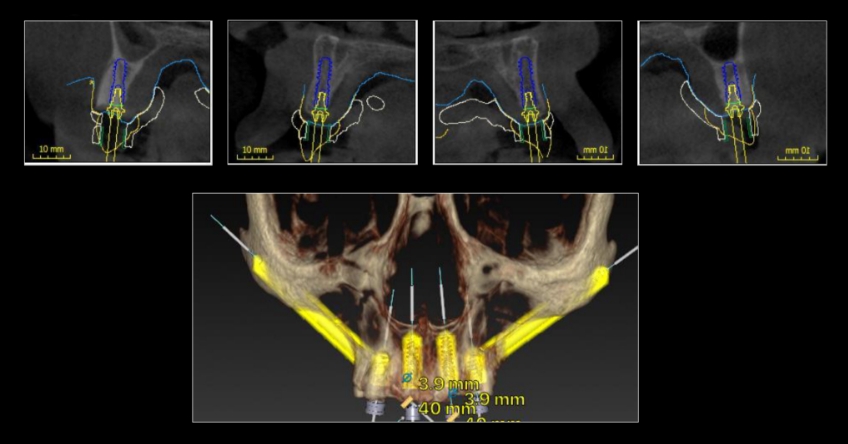

The challenge is that bone availability is limited to her premaxilla, so we must either graft the sinuses to incorporate distal implants or bypass the sinuses and place one ZI bilaterally. Both approaches are perfectly doable and predictable because they’re supported in the scientific peer-reviewed dental literature. They also present nuanced implications that need to be reviewed and understood by the treating team and the patient, who is the ultimate decision-maker.

Her pneumatized sinuses do not allow grafting and implant placement simultaneously. This means we would need a staged approach — perform an initial procedure limited to grafting and a subsequent procedure for implant placement.

This translates to a significant increase in treatment time and financial commitment by the patient. However, bypassing the sinuses and placing a ZI bilaterally would expedite the overall treatment time and represent a financial benefit.

Once the patient understood the nuances between graft vs. a graft-less solution, she opted for a combination of anterior and ZIs instead of grafting the sinuses.

Ultimately, the patient was treated using a combination of traditional and zygomatic implants, allowing her to transition into the definitive prosthesis uneventfully and in a reasonable time frame. This prosthetic design aimed to improve the distribution of occlusal forces and provide enhanced structural support for the final prosthesis.